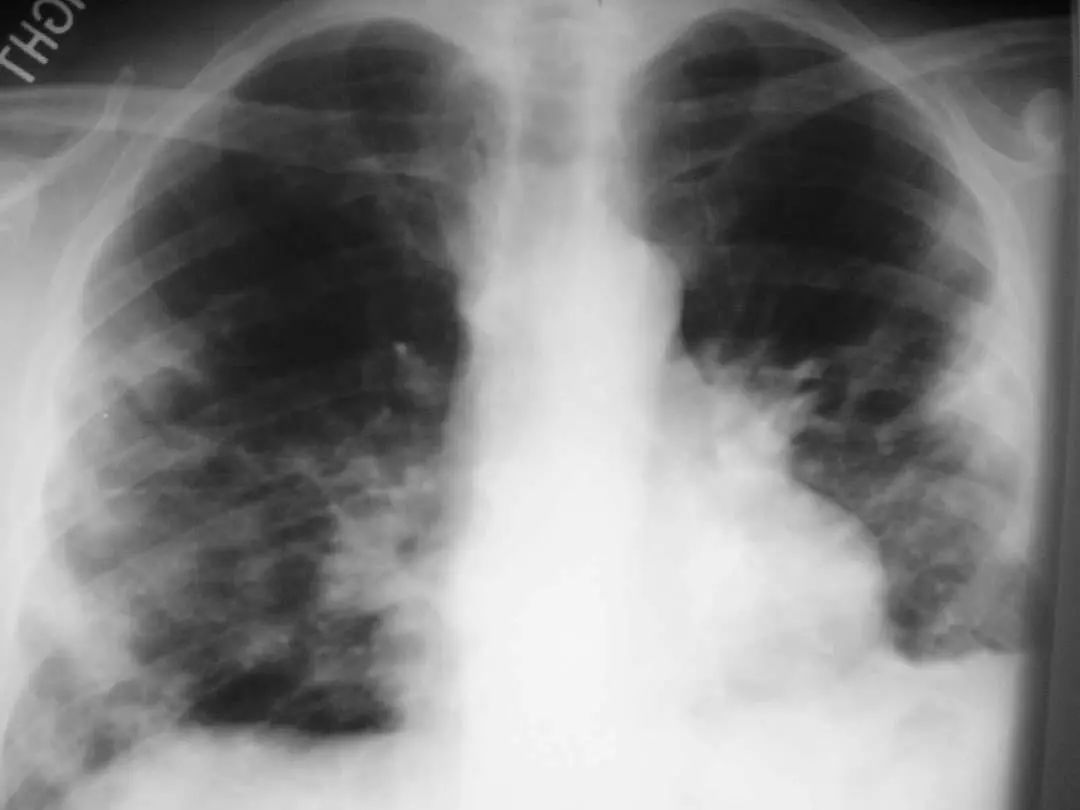

图1.1 细菌性肺炎。右上叶肺炎患者的放射影像。胸廓前后径增大,提示有慢性阻塞性肺疾病(COPD)。